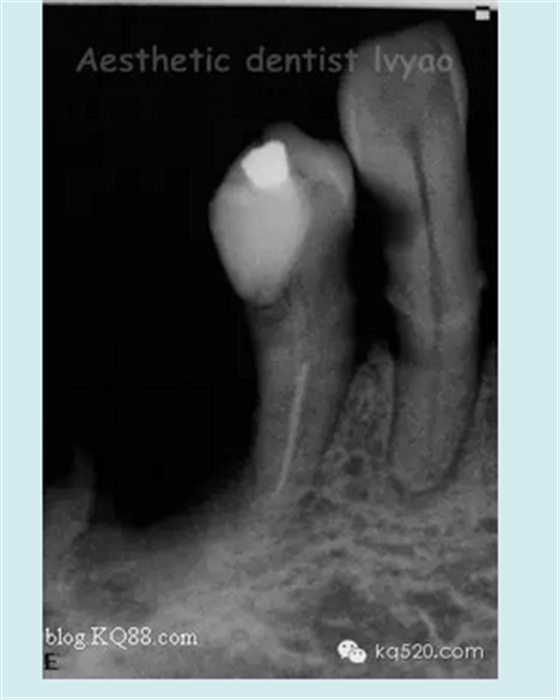

右下34修復(fù)前X片(牙槽骨吸收,基牙達到2度松動)